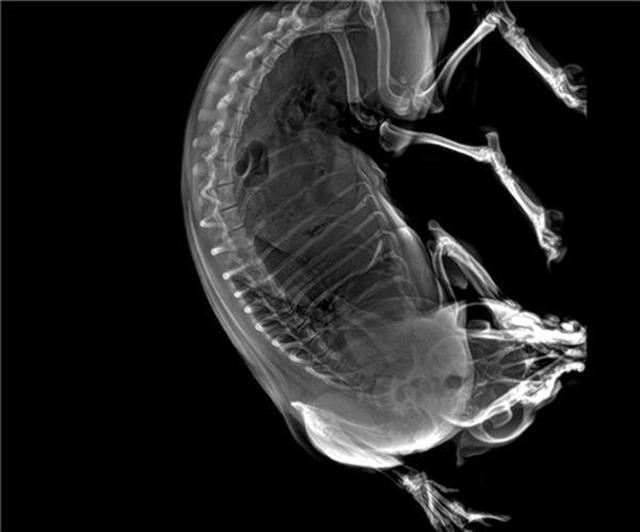

宠物DR的工作原理是X光线穿透动物体后在屏幕或者胶片上面显示体内影像。辅助宠物医生读片跟准确的治疗,宠物DR显示是宠物医院诊所的配置,提高了诊断的效率。DR的检测效率比X线高44%,成像快采集时间10MS以下。3秒左右就可以看到检查图像。常规的胸部DR还要几分钟。所以宠物DR的出片速度是非常快的。很高的空间分辨率低噪音。可以获得高清图像,提高检测正确率避免误诊等等问题。数字化图像的优势是可以保留原始数据,图片识别,二三维的重建,医学影像学实现全数字化和无胶片化铺平了道路。提供照片打印服务,防止照片丢失而重复照片。有针对性的对图像进行处理,以提高诊断率。宠物DR的辐射量很低的,对人体的辐射风险不大。